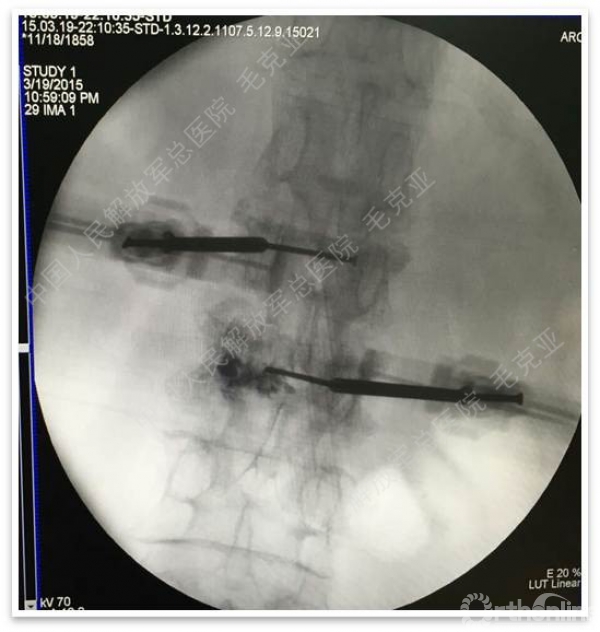

毛克亚:新型弯角椎体增强装置的研制与临床应用研究

导语:随着社会老龄化的不断加速,骨质疏松性椎体压缩骨折作为一种普遍存在的老年骨科疾病已经成为现今骨科界的一个热点话题。传统的保守疗法治疗效果不佳,而现有的椎体增强技术又具有多种风险和缺陷。针对这种现状,中国人民解放军总医院毛克亚教授提供了一种新的解决方法。